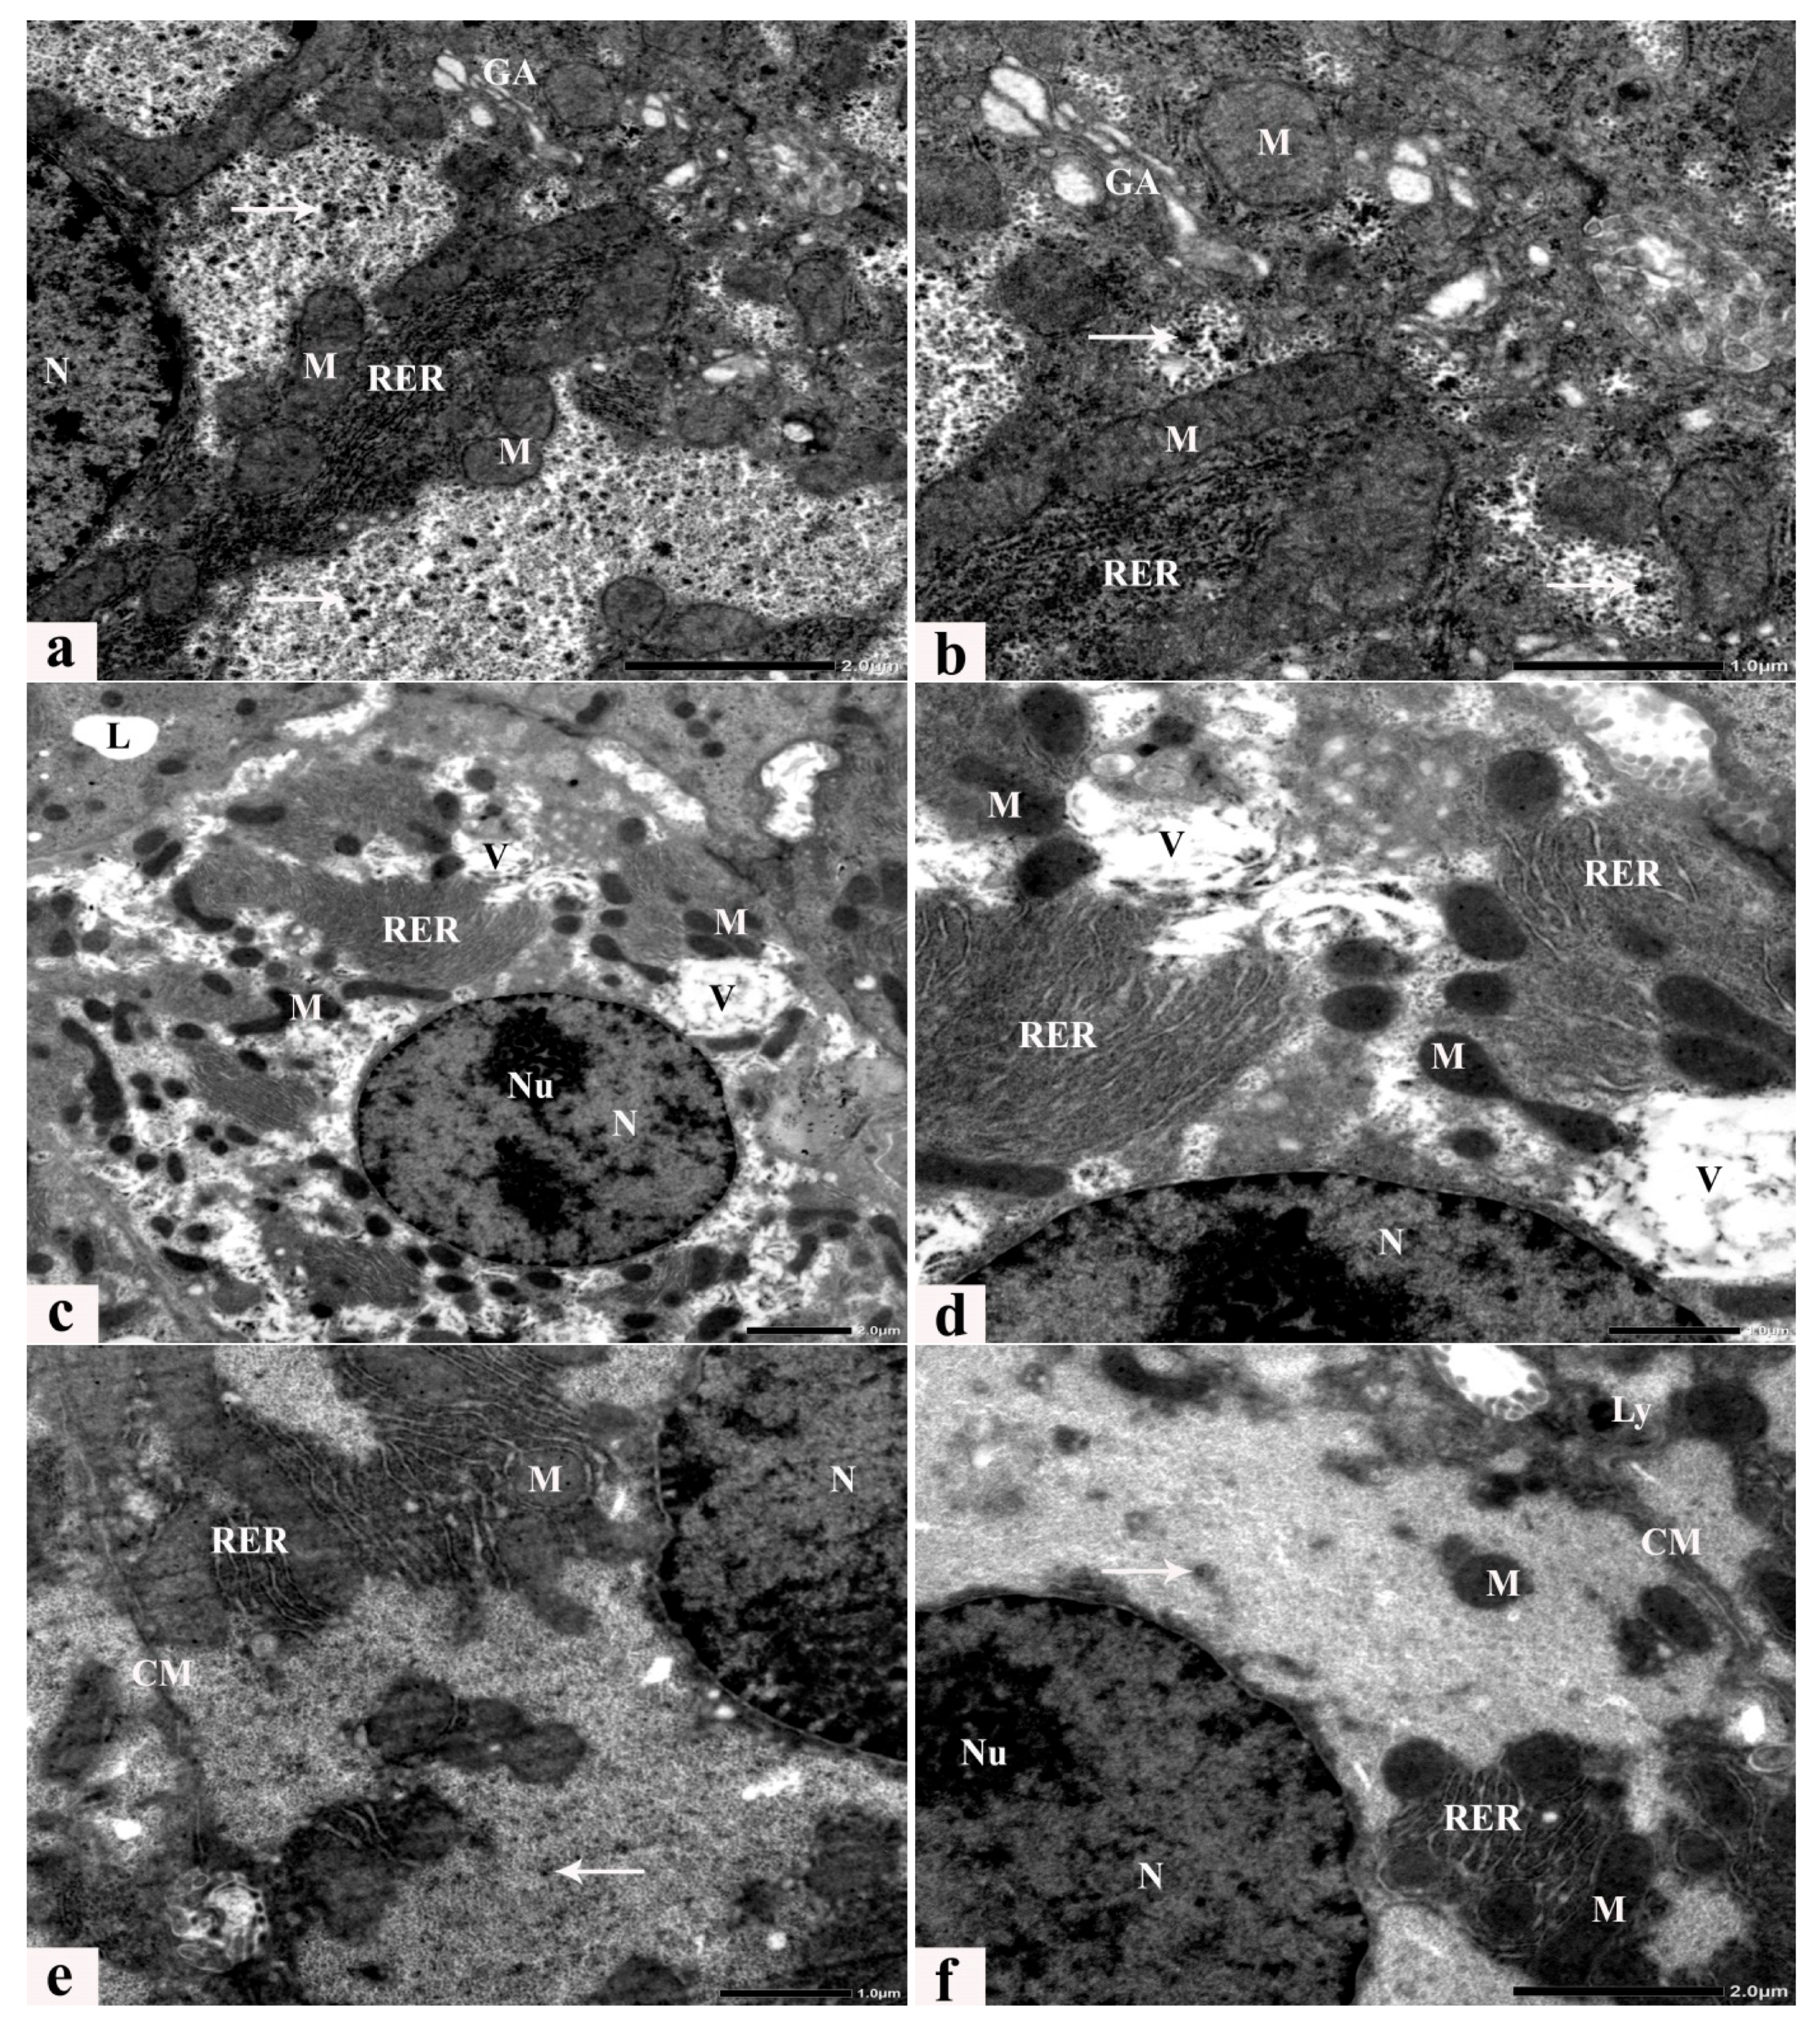

3.6. Ultrastructure Alterations